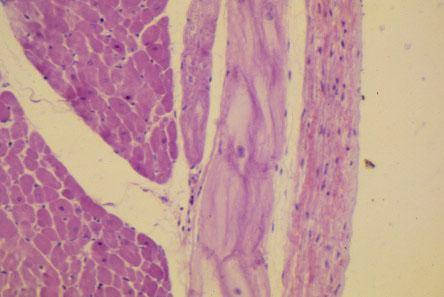

VI-6 (5) Slide 32, Heart - Purkinje Fibers (H&E). Medium power view of endocardium with Purkinje fibers (large pale cells) and myocardium. Note that the sarcoplasm appears more clear than that seen in cardiac myocytes.